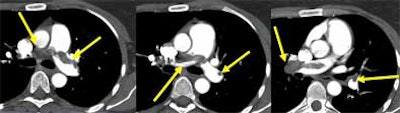

![]() |

| Intraluminal filling defects reveal pulmonary embolism in target sign (above), and tram track sign (below). Images courtesy of Dr. John Mayo. |

Once a clot is spotted, radiologists must test the theory by asking themselves how the alleged embolus is able to remain immobile, while the pulmonary vasculature goes into high flow "like a toilet flushing," once per second, he said. Is the "embolus" immobile because it's hooked into a vessel? If not, it might be an artifact. True clots should have a visible means of escaping the blood flow. Similarly, he said, a "clot" that appears on just one or two sections on both the right and left sides might be a flow artifact.